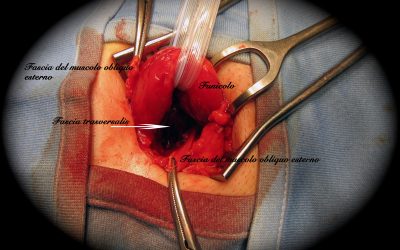

Ernioplastica inguinale con protesi interfasciale: note di tecnica chirurgica

di Enrico Ganz Introduzione Attualmente una delle più comuni tecniche di ernioplastica per la correzione dell’ernia inguinale monolaterale non recidiva, sia non complicata, sia complicata da strangolamento (27), prevede l’utilizzo di una rete protesica...